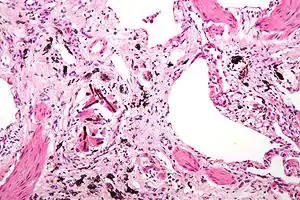

Micrograph of asbestosis with prominent ferruginous bodies. H&E stain.

Micrograph of asbestosis with prominent ferruginous bodies. H&E stain.